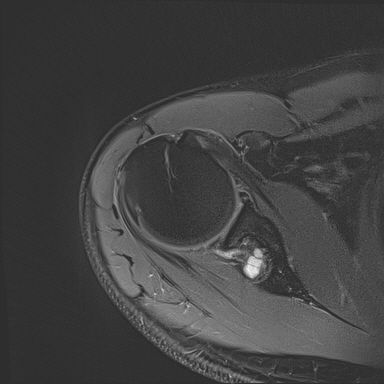

어깨 mri 좀 봐주세요 물혹있다고 하는데 수술해야 하나요?

하도 안 나아서 우측 견관절도 mri 촬영을 했는데 물혹이 있네요

이거 수술해야 하나요?

팔에 힘이 안들어간다거나 방사통이나 아파서 잠을 깬다는점등은 현재 없는데...

이거 때문에 승모근이 잘 뭉치고 목이 뻣뻣한가요?